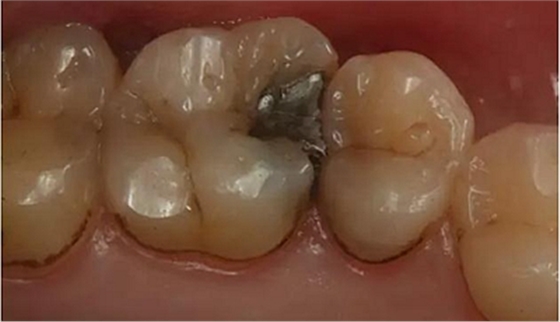

患者男性,35歲,B6銀汞充填后食物嵌塞,要求重新充填,口內(nèi)檢查見B6近中鄰頜面銀汞充填物,局部缺損,有繼發(fā)齲,去除原充填物及繼發(fā)齲,發(fā)現(xiàn)齲壞位于牙齦下方,給予冠延長手術(shù),同期嵌體預(yù)備,后一次性取模。(同樣設(shè)計(jì)為齦上邊緣)

硅橡膠取模后,灌注模型,科爾琥珀樹脂制作嵌體。